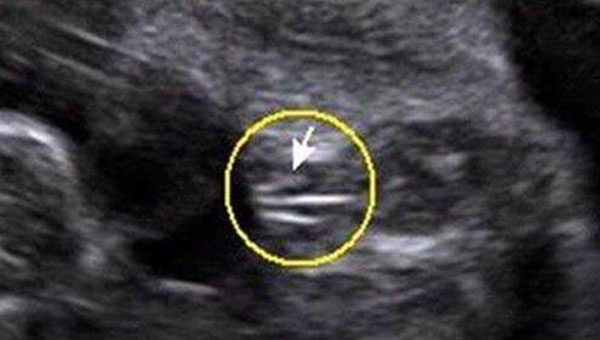

女宝宝从b超图中看到的影像,两腿中间有三条白线标志,这是女孩的外生殖器特征,也就是女宝宝的小***。

男宝宝从b超图中看到的影像,两腿中间有小亮点或小突起,这是男孩的外生殖器特征,也就是男宝宝的小JJ。